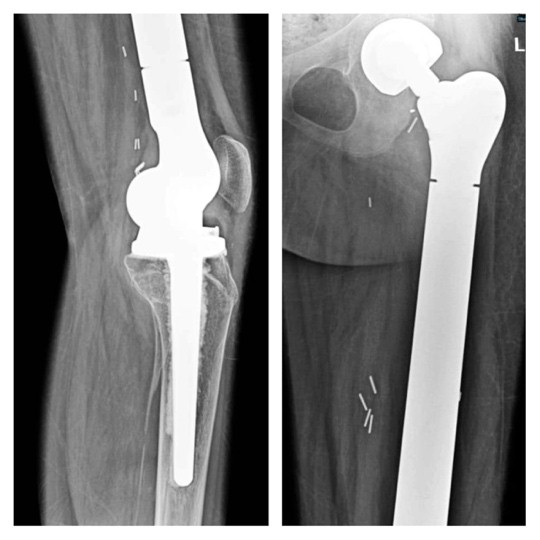

Post-operative course was uneventful with drain removed on post-operative day 3 and PT discharged on post-operative day 5. Abductor muscle strengthening exercises started on bed on post-operative day 2 without weight bearing. Post-operative X-ray showing well fitted prosthesis as shown in Fig. 5. Four weeks bed rest given for healing of mesh then started full-weight-bearing mobilization with walker f/b stick support and then without support. Strengthening and range of motion exercise titrated for individual need. Past follow-up was in June 2025. As patient attained menarche there will be low chance of limb length discrepancy, but even if occurred can be managed conservatively by shoe lift. Follow-up will be 6 monthly with radiograph of local site for recurrence with contrast-enhanced computed tomography (CT) thorax for metastasis.

Figure 5: Post-surgery X-ray.